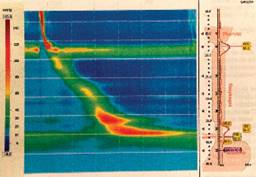

La manometría reporta esfínter esofágico superior de tono normal y relajación completa, motilidad esofágica efectiva, unión esofagogástrica tipo 1, con esfínter esofágico inferior con presión basal promedio normal, relajación de la unión esofagogástrica normal (Figura 3).

Figura 3: Manometría esofágica; esfínter esofágico superior de tono normal y relajación completa, motilidad esofágica efectiva, esfínter esofágico inferior con presión basal promedio normal, obstrucción al flujo de salida de la unión gastroesofágica.